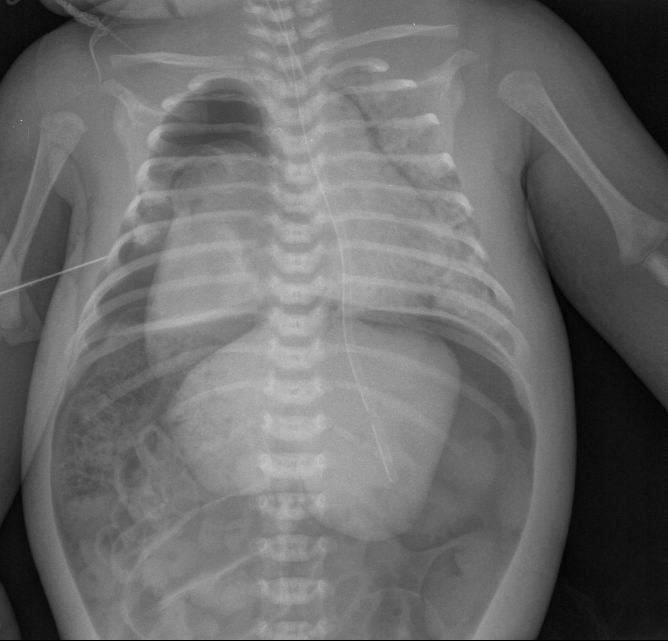

Ребёнок с рождения находится в РАО новорожденных, причину пока не скажу. На момент снимка - возраст 1 месяц. Снимок сделан в связи с резким ухудшением состояния, падением сатурации.

Итак: в данном случае пренатально был выставлена правосторонняя диафрагмальная грыжа, родоразрешение было проведено на республиканском уровне, после чего ребёнком сразу начали заниматься детские хирурги. Была проведена торакоскопия, на которой выявили выраженную гипоплазию и апневматоз правого лёгкого. Кроме того у ребёнка по ходу случилось массивное внутрижелудочковое кровоизлияние и сформировалась прогрессирующая гидроцефалия. В связи с бесперктивноситью оперативного лечения, ребёнок был переведён в РАО нашей больницы в качестве хосписного больного.

CR0001.jpg

Поскольку состояние ребёнка относительно стабилизировалось , начали подумывать о возможноти всё- таки провести опративное лечение, но произошло резкое ухудшение состояния ребёнка в связи с тем, что лопнул рудимент правого лёгкого . Получена рентгенологическая картина почти всех возможных вариантов синдрома утечки воздуха, в т. ч. и пневмоперитонеум , поскольку правого купола диафрагмы не было и воздух из плевральной полости заполнил брюшную полость и дал напряжённый пневмоперитонеум:

CR0002.jpg